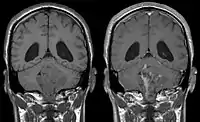

Ependymoma of 4.ventricle in MRI. Ependymoma of 4.ventricle in MRI.

Ependymoma of 4.ventricle in MRI. Ependymoma of 4.ventricle in MRI. Left without, right with contrast-enhancement.

Ependymoma of 4.ventricle in MRI. Left without, right with contrast-enhancement.